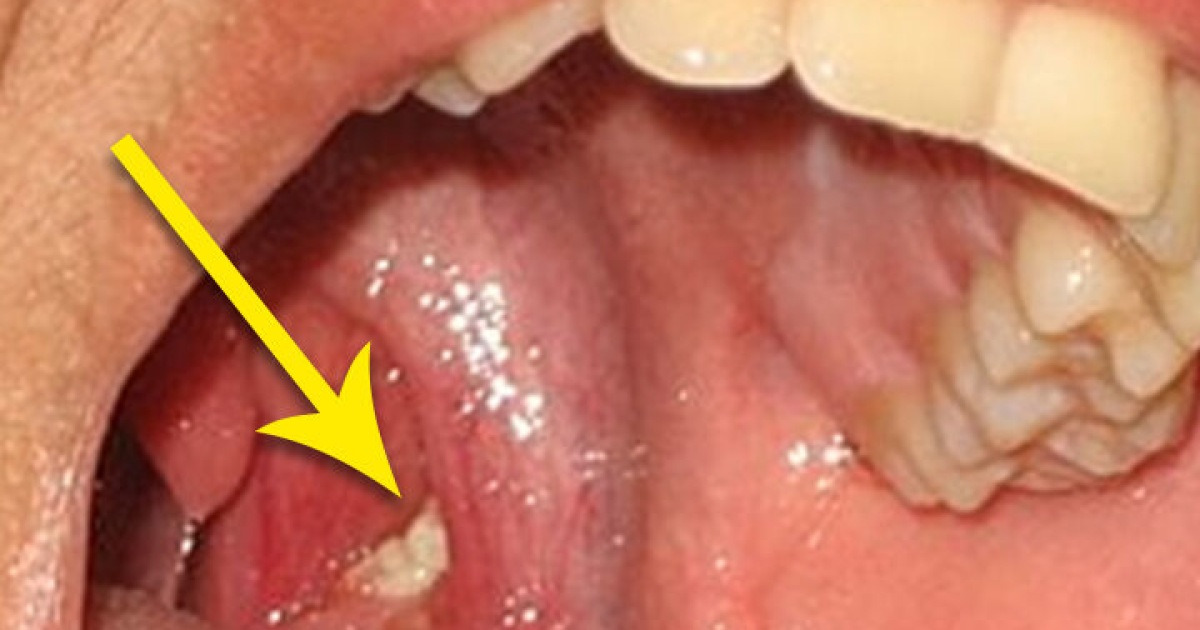

입안의 편도에는 작은 구멍이 있습니다.이 구멍에 세균이나 음식 찌꺼기가 뭉쳐서 굳어진 것을 편도결석이라고 합니다.

1~2mm 정도로 쌀알만한 크기의 알갱이가 보통이지만 더 클 경우 육안으로 확인이 가능할 정도입니다.

흰색이나 노란색 알갱이는 깨지기 쉽고 심한 입냄새를 동반하기 때문에 일상생활에서 사람을 상대할 때 불쾌감을 느끼게 합니다.